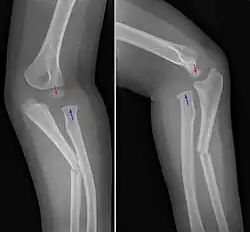

Die Diagnose einer Monteggia-Fraktur wird im konventionellen Röntgenbild gestellt. Dabei wird der Unterarm mit dem Ellenbogen von vorne und von der Seite geröntgt. Insbesondere in der seitlichen Betrachtung kann man beurteilen, inwieweit der Speichenkopf ausgerenkt ist. Der Radiuskopf muss in beiden Ebenen (!) auf das Capitulum humeri zentrieren.

Häufige Ursache des Nicht-Erkennens ist, dass der Ellenbogen nicht oder nicht beurteilbar mit abgebildet ist.